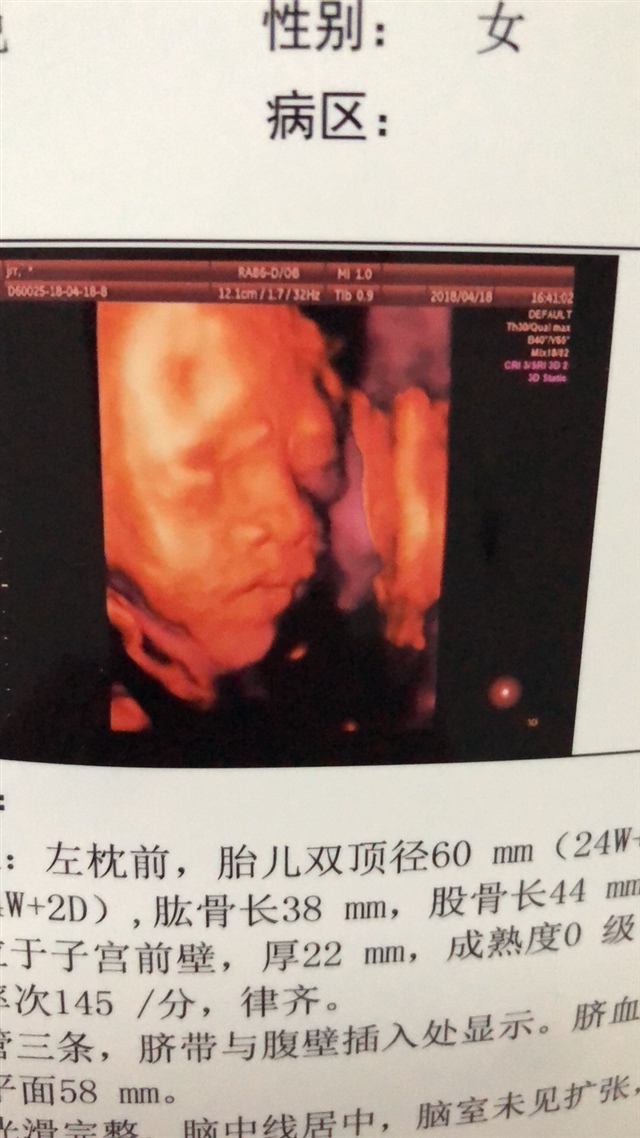

23周照的

多少周照的